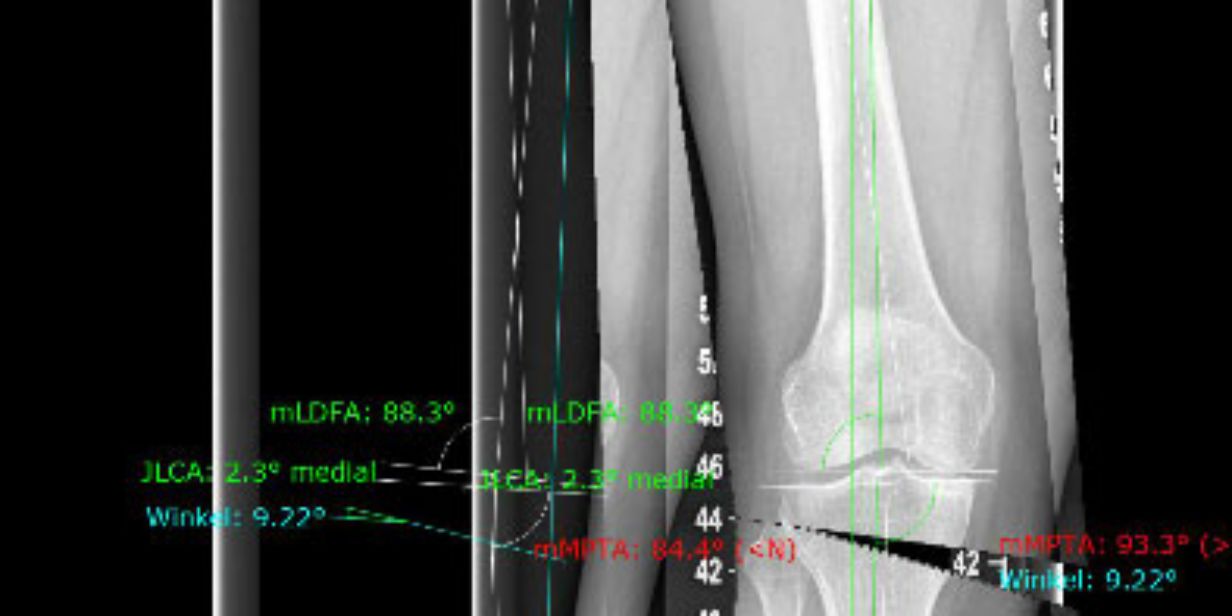

OBein, XBein Korrektur Medikon Forchheim. Im Oktober 2019 wurde das linke Bein korrigiert und gleichzeitig ein CMI-Meniskusimplantat eingesetzt Ab wann müssen X-Beine oder O-Beine operiert werden? Wurde bereits eine konservative Therapie versucht, die über einen längeren Zeitraum nicht zum Erfolg geführt hat, kann eine Knochenumstellung (Osteotomie) die Achsfehlstellung korrigieren.